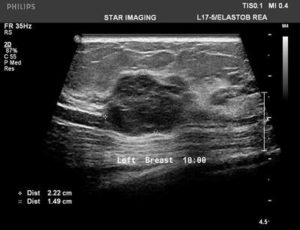

39yr old lady with history of lump in the left breast UIQ, No previous imaging done. No positive family history for CA Breast/Ovary. Pre-Menopausal Status.

Mammography- Fairly well circumscribed predominantly sold lesion in the left breast UIQ with partially obscured margins. No spiculations. No associated microcalcifications noted. Sonography: Well defined hypoechoiec lesion with smooth margins.

Low-grade Mucinous Carcinoma ER?PR- +ve HER-2 NEU -VE